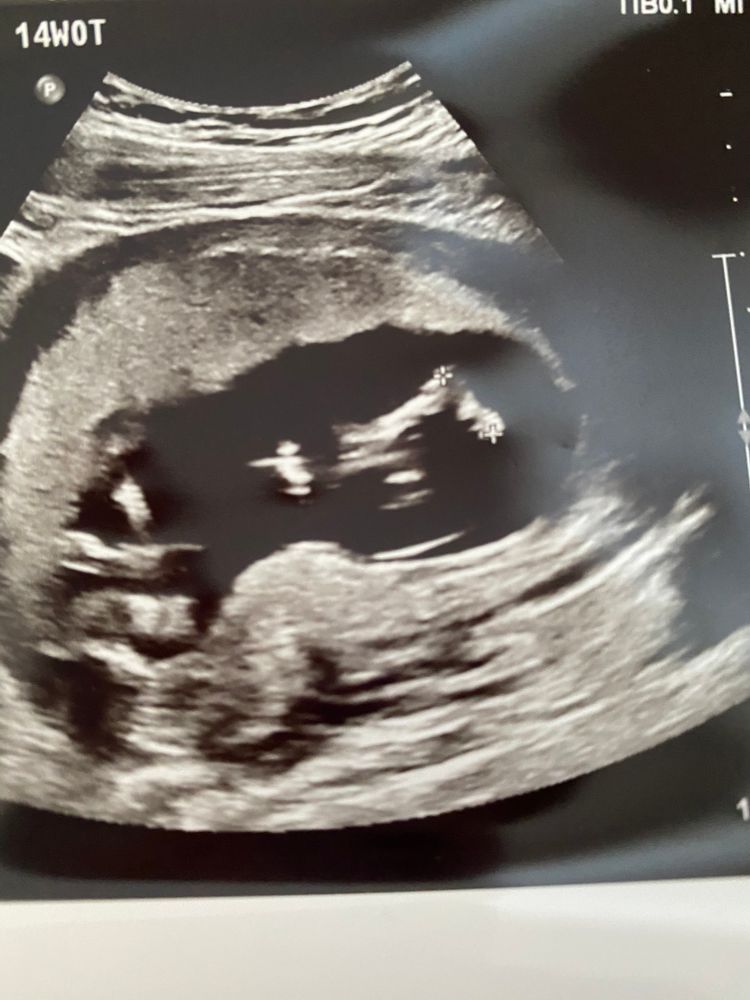

14 недель,узи

Кто то помнит размеры ребёночка, на таком сроке? Окружность головы и тд..Bpd ( окружность головы всего лишь 2.39) По нормам должно быть больше

Вес у нас 100 грамм. И по узи теперь опережаем на 4 дня. Врач ничего не сказала, кроме того что все разные дети. И даже измерили длину ступни😅Фотку получила с ножкой-1,30 см☺️ А пол не разглядели, спрятал